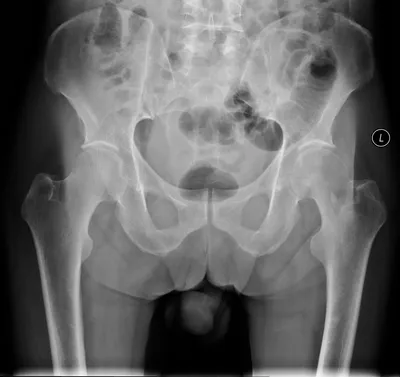

Left sided pubic ramal fractures

XRAYPelvisfracture

4/23/2026